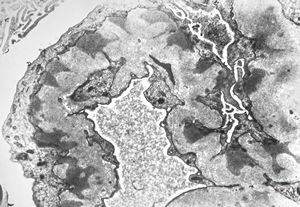

F,14y. | Alport syndrome - split and laminated, thick/thin basement membranes